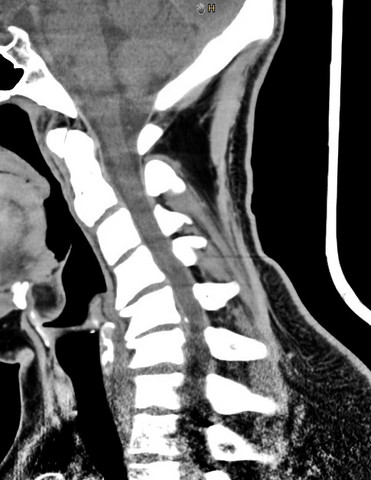

Ist Das Ein Bandscheibenvorfall Ct Schule Gesundheit Und Medizin Gesundheit